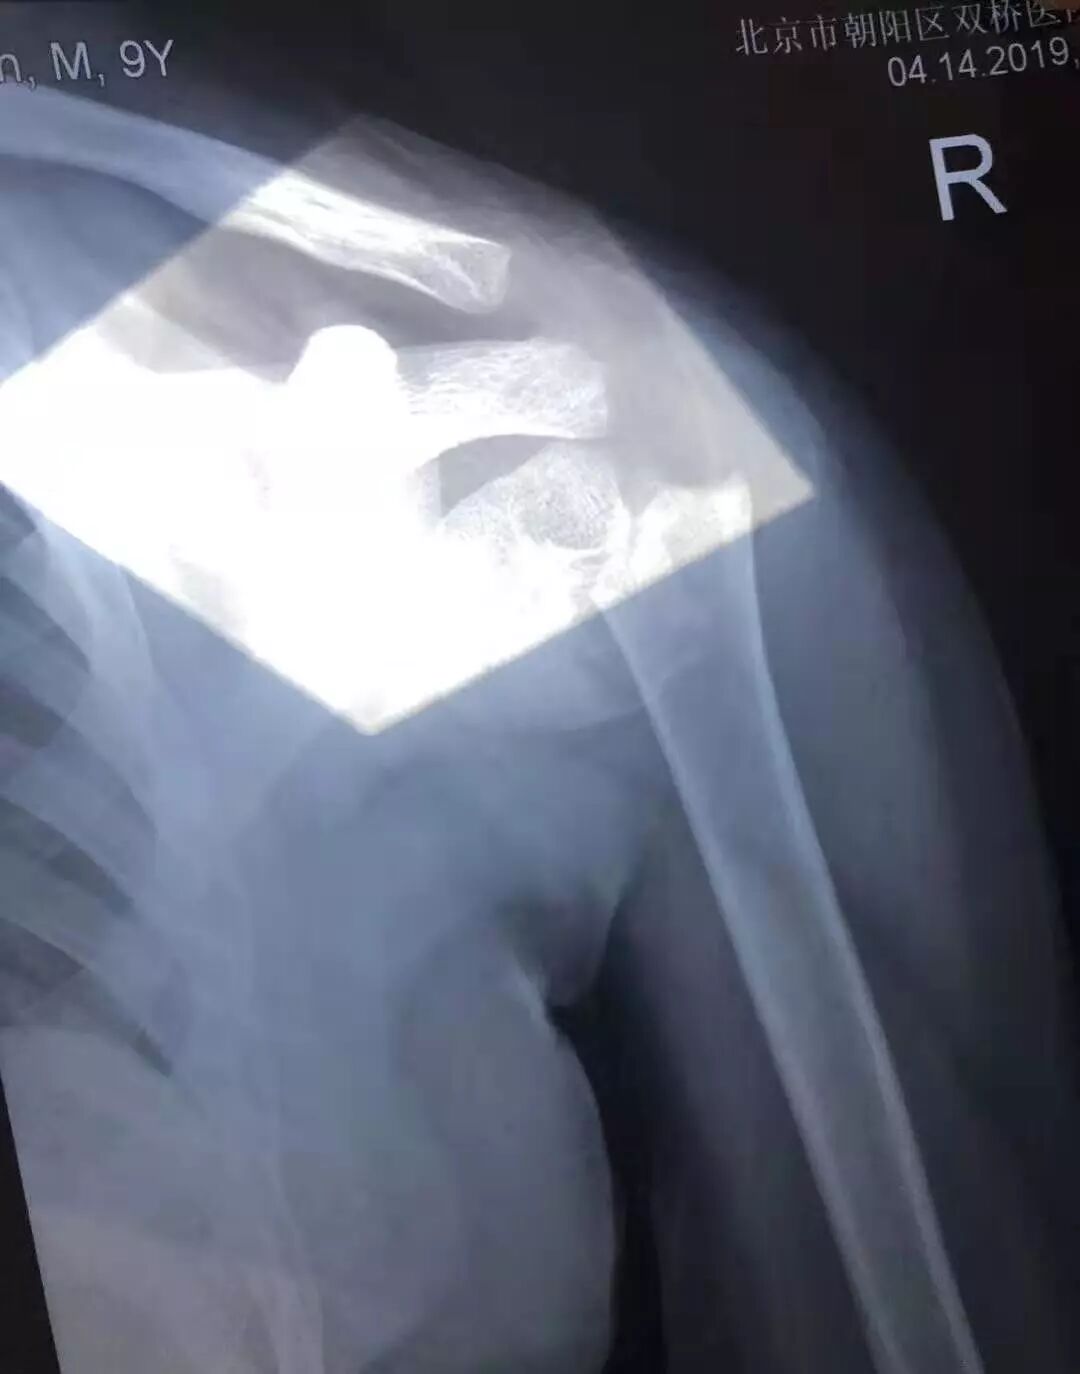

小患者摔伤时的X光片

但是王先生还是想坚持保守治疗,此时他想起了京城闻名遐迩的正骨圣手“双桥老太太”,经过网上搜索找到了双桥老太太的嫡孙罗勇院长。罗勇院长仔细审阅了小患者的X片,对受伤部位进行了手法触诊,诊断为“左肱骨外科颈骨折移位”,经过罗院长几次手法正骨治疗后,小患者左肩骨折部位恢复的很好。